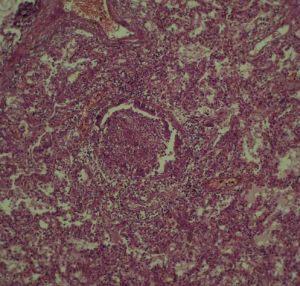

其他輔助檢查:影像學檢查:絕大部分患者在起病早期即有胸部X線檢查異常,多呈斑片狀或網狀改變。起病初期常呈單灶病變,短期內病灶迅速增多,常累及雙肺或單肺多葉。部分患者進展迅速,呈大片狀陰影。雙肺周邊區域累及較為常見,而胸腔積液、空洞形成以及肺門淋巴結增大等表現則較少見。對於胸片無病變而臨床又懷疑為本病的患者,1~2天內要複查胸部X線檢查。胸部CT檢查以玻璃樣改變最多見。肺部陰影吸收、消散較慢;陰影改變與臨床症狀體徵有時可不一致。